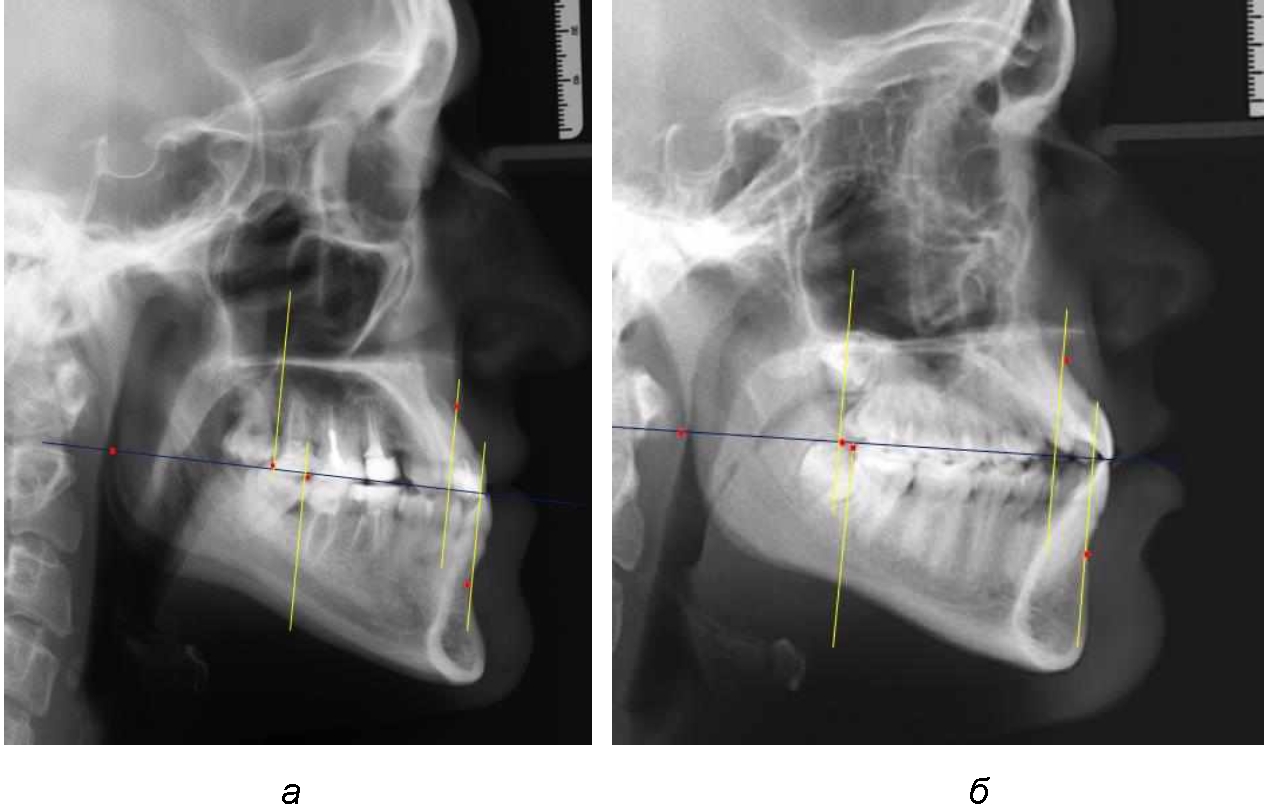

При всех вариантах положения верхней челюсти, было отмечено, что альвеолярно-денталь-ные размеры верхних зубо-челюстных дуг были близки по значению к аналогичным размерам нижней челюсти и разница в размерах не превышала 1,0–1,5 мм, а средняя величина различия показателей составляла (1,07 ± 0,54) мм.

Расстояние от конструируемой точки окклюзионной плоскости на ветви челюсти («rmРOcP») до апикальных точек Downs на обеих челюстях также коррелировало между собой, и средняя величина различия показателей составляла (1,23 ± 0,69) мм. Проекция нижней апикальной точки на окклюзионную линию, как правило, располагалась несколько кпереди проекции верхней апикальной точки, на величину около 1 мм, что соответствовало оптимальным данным Wits-анализа.

Аналогичное расстояние было отмечено и при расположении дистальных окклюзионных точек верхней и нижней челюсти (рис. 2).

Рис. 2. Положение апикальных точек и челюстей при нормопозиции (а), антепозиции (б) и ретропозиции (в) верхней челюсти